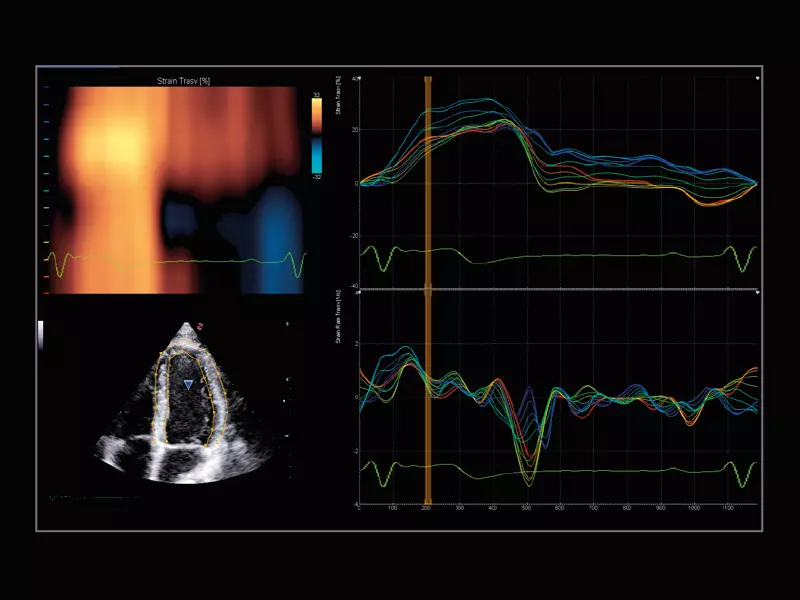

MyLab™C25 - Xstrain

MyLab™C25 - Xstrain

MyLab™9 Platform - XStrain™ 2D speckle tracking technologies for global and regional function

MyLab™9 Platform - XStrain™ 2D speckle tracking technologies for global and regional function

MyLab™Sigma - Left Ventricle XStrain 2D analysis

MyLab™Sigma - Left Ventricle XStrain 2D analysis

MyLab™X8 Platform - Zero-click strain evaluation with XStrain™2D

MyLab™X8 Platform - Zero-click strain evaluation with XStrain™2D

MyLab™X90 - XStrain™ LV Automatic assessment of global longitudinal strain in the left ventricle

MyLab™X90 - XStrain™ LV Automatic assessment of global longitudinal strain in the left ventricle

MyLab™X5 - XStrain

MyLab™X5 - XStrain

MyLab™X6 - XStrain

MyLab™X6 - XStrain

MyLab™X7 - XStrain

MyLab™X7 - XStrain